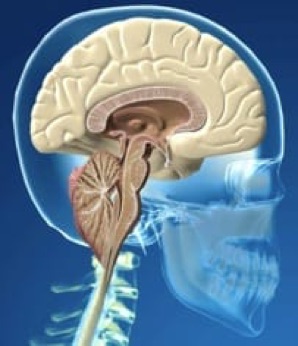

Figure 1.- Schéma montrant la descente des amygdales et l’augmentation conséquente de l’espace supracérébelleux, lorsque tout le cervelet se dirige vers le canal vertébral, dans le syndrome d’Arnold-Chiari I.